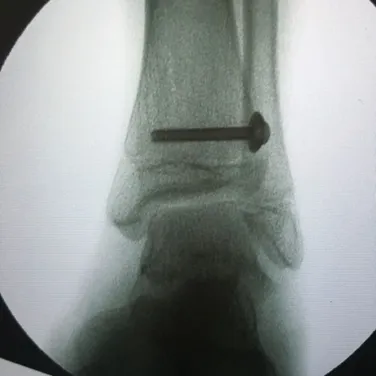

Nerves may be compressed from tight ligaments, inflamed tendons, tumors, fracture fragments, varicose veins, scar tissue or injuries to the foot that cause the foot and ankle to be misshapen (severe flatfoot).  Nerve compression may cause significant discomfort with weightbearing.  Night pain and pain while the patient is nonweightbearing are common as well.  The most important a physician can do is to direct the treatment to the cause of the problem.  If the foot is misshapen causing no pain (numbness, tingling or shooting), the nerve does not need surgery, the foot and ankle bones might.  The wrong diagnosis can be disastrous.  If a tumor or varicose vein is causing the pain they may need to be resected to allow the nerve to function normally.  Anything abnormally applying pressure to the nerve may cause symptoms.  If a tight ligament is identified, it has to be released to allow the nerve to function normally.  Occasionally nerve conduction studies are performed to assess the degree of nerve compression and nerve damage. The common peroneal nerve is located at the fibular neck, just to the outside of the knee.  If the nerve is injured or damaged, it can cause a dropfoot due to paralysis of the muscles that it innervates.

Nerves may be compressed from tight ligaments, inflamed tendons, tumors, fracture fragments, varicose veins, scar tissue or injuries to the foot that cause the foot and ankle to be misshapen (severe flatfoot).  Nerve compression may cause significant discomfort with weightbearing.  Night pain and pain while the patient is nonweightbearing are common as well.  The most important a physician can do is to direct the treatment to the cause of the problem.  If the foot is misshapen causing no pain (numbness, tingling or shooting), the nerve does not need surgery, the foot and ankle bones might.  The wrong diagnosis can be disastrous.  If a tumor or varicose vein is causing the pain they may need to be resected to allow the nerve to function normally.  Anything abnormally applying pressure to the nerve may cause symptoms.  If a tight ligament is identified, it has to be released to allow the nerve to function normally.  Occasionally nerve conduction studies are performed to assess the degree of nerve compression and nerve damage. The common peroneal nerve is located at the fibular neck, just to the outside of the knee.  If the nerve is injured or damaged, it can cause a dropfoot due to paralysis of the muscles that it innervates.  Nerves may be compressed from tight ligaments, inflamed tendons, tumors, fracture fragments, varicose veins, scar tissue or injuries to the foot that cause the foot and ankle to be misshapen (severe flatfoot).  Nerve compression may cause significant discomfort with weightbearing.  Night pain and pain while the patient is nonweightbearing are common as well.  The most important a physician can do is to direct the treatment to the cause of the problem.  If the foot is misshapen causing no pain (numbness, tingling or shooting), the nerve does not need surgery, the foot and ankle bones might.  The wrong diagnosis can be disastrous.  If a tumor or varicose vein is causing the pain they may need to be resected to allow the nerve to function normally.  Anything abnormally applying pressure to the nerve may cause symptoms.  If a tight ligament is identified, it has to be released to allow the nerve to function normally.  Occasionally nerve conduction studies are performed to assess the degree of nerve compression and nerve damage. The common peroneal nerve is located at the fibular neck, just to the outside of the knee.  If the nerve is injured or damaged, it can cause a dropfoot due to paralysis of the muscles that it innervates.